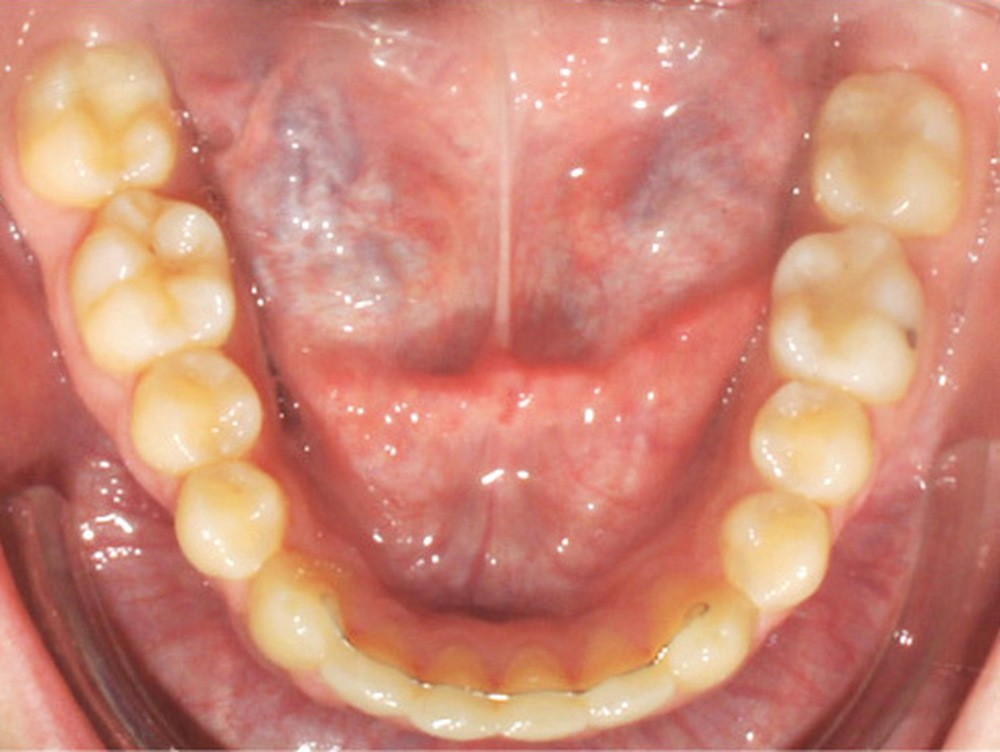

Examen endobuccal (fig. 2a-e)

L’arcade maxillaire est asymétrique, en hémi-lyre droite. Elle présente une mésio-position du secteur 1 en lien avec un encombrement antérieur estimé à 4 mm, se traduisant par une palato-position de la 12 et une rotation de la 11. On observe également des mésio-rotations des premières molaires et une palato-version incisive. L’arcade mandibulaire est ellipsoïde et présente un léger encombrement incisif (1 mm).

Concernant les relations occlusales, on observe une classe II complète subdivision droite. Le surplomb est absent et le recouvrement augmenté, estimé à 4 mm, a provoqué une usure des bords libres de 11 et 21 par attrition. Dans la dimension transversale, on constate une endoalvéolie maxillaire, ainsi qu’une concordance des médianes incisives entre elles, mais toutes deux déviées à droite par rapport au plan sagittal médian.